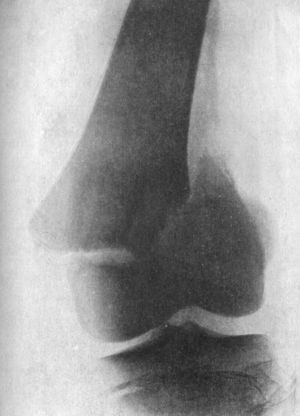

123.Lower End of Femur from an Advanced Case of Tuberculous Arthritis of the Knee231

124.Advanced Tuberculous Disease of Knee, with Backward Displacement of Tibia233